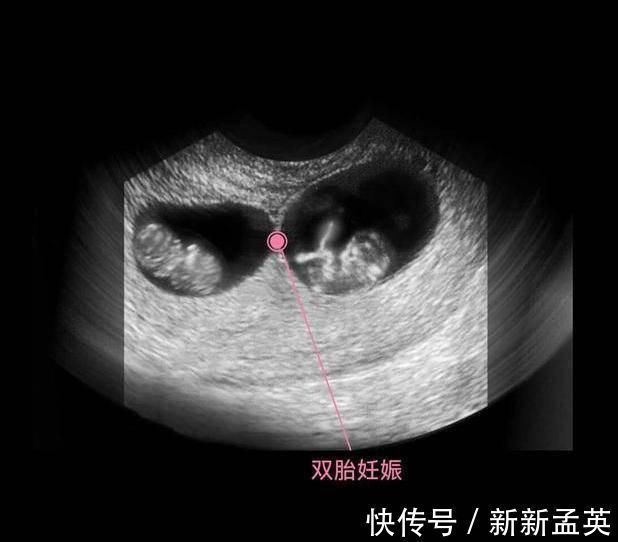

在上图可见是个双胎妊娠,胎儿具有一个很大的头,和身材很不对称,是不是跟出生后的胎宝宝有点像了?其实此时的头部比例更悬殊,宝宝的额面部器官发育很明显,心脏也开始了跳动,出现了胎心,此时做B超,可见胎心胎芽。